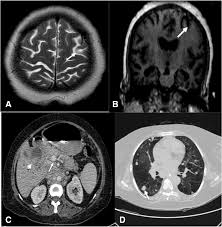

What Is The First Sign Of Bladder Cancer / Groundbreaking Urine Test That Can Spot Bladder Cancer Proves 100 Accurate In Trials Australiannewsreview - Blood in the urine is usually the first warning sign of bladder cancer;. Blood or blood clots in the urine Sometimes, people with bladder cancer do not have any of these changes. People with bladder cancer may experience the following symptoms or signs. The technical term for this condition is hematuria. The early signs of bladder cancer are related to a tumor that has not yet metastasized.

The technical term for this condition is hematuria. The tumor can be removed with surgery , and treatments such as chemotherapy and radiation therapy can be used to help kill any remaining cancer cells and to keep new cancer cells from growing. This is the most common symptom of bladder cancer and occurs in the vast majority of people with bladder cancer. Bladder cancer is the 4 th most common cancer among veterans. In this article, we will explore bladder cancer in further detail including types of bladder cancer, early warning signs of bladder.

Early Signs Of Bladder Cancer Youtube from i.ytimg.com However, it is also associated with a number of benign medical problems such as urinary tract infection, kidney/bladder stones, and benign tumors, and does not mean a person has bladder cancer. In this article, we will explore bladder cancer in further detail including types of bladder cancer, early warning signs of bladder. Blood in the urine or hematuria is the most common, and often the first, sign of bladder cancer. Blood in urine (hematuria), which may cause urine to appear bright red or cola colored, though sometimes the urine appears normal and blood is detected on a lab test Or, the cause of a symptom may be a different medical condition that is not cancer. Blood particles might also be microscopic and detected only in a urinalysis ordered by a doctor. The urine may look orange or pink. Bladder cancer is caused by cells that mutate (change) and begin to grow in an uncontrolled way.

There are other symptoms to watch for as well. According to the american cancer society, the relative survival rates for all stages of bladder cancer are: Gross hematuria means you can see the blood in your urine, which may appear pink, red, or brownish in color. Around 80% to 90% of patients diagnosed with bladder cancer have this symptom. It may be present on a regular basis or disappear and reappear over the course of days or weeks. In most cases, the first sign of bladder cancer is blood in the urine. Thus, they are related to the occupation of space inside the bladder. Other symptoms include pain or burning sensation during urination, frequent urination, feeling the need to urinate many times throughout the night, feeling the need to urinate, but not being able to pass urine and lower back pain on one side of the body. The symptoms of stage 4 bladder cancer include tiredness, weakness, and pain. The tumor can be removed with surgery , and treatments such as chemotherapy and radiation therapy can be used to help kill any remaining cancer cells and to keep new cancer cells from growing. Blood or blood clots in the urine Bladder cancer signs and symptoms may include: People with bladder cancer may experience the following symptoms or signs.

This is the most common symptom of bladder cancer and occurs in the vast majority of people with bladder cancer. Blood in the urine is usually the first warning sign of bladder cancer; Chemo (with or without radiation) is typically the first treatment when bladder cancer has spread to distant parts of the body (m1). Blood in the urine can be a sign of bladder cancer, either visible to the eye or picked up by routine testing. Thus, they are related to the occupation of space inside the bladder.

Can Recurrent Uti Symptoms Be A Sign Of Cancer Cxbladder from www.cxbladder.com Around 80% to 90% of patients diagnosed with bladder cancer have this symptom. When cancer starts to spread, it frequently spreads to the lymph nodes nearest the bladder first. Unfortunately, the blood is often invisible to the eye. This is the most common symptom of bladder cancer and occurs in the vast majority of people with bladder cancer. It may be present on a regular basis or disappear and reappear over the course of days or weeks. This is the most common early symptom of bladder cancer and typically the first sign of bladder cancer that is seen. Chemo (with or without radiation) is typically the first treatment when bladder cancer has spread to distant parts of the body (m1). Sometimes, people with bladder cancer do not have any of these changes.

Thus, they are related to the occupation of space inside the bladder. People with bladder cancer may experience the following symptoms or signs. Kidney or bladder cancer can cause this symptom, but it could also be due to an. Gross hematuria means you can see the blood in your urine, which may appear pink, red, or brownish in color. Chemo (with or without radiation) is typically the first treatment when bladder cancer has spread to distant parts of the body (m1). Early signs of bladder cancer are similar to those of a bladder infection. Continue learning about bladder cancer Blood in the urine (hematuria) is often the most common sign of bladder cancer. Bladder cancer signs and symptoms may include: They include urinary frequency, urgency, and pain and burning with urination. Blood particles might also be microscopic and detected only in a urinalysis ordered by a doctor. It may be present on a regular basis or disappear and reappear over the course of days or weeks. Unfortunately, the blood is often invisible to the eye.

Blood in the urine (hematuria) is often the most common sign of bladder cancer. Or, the cause of a symptom may be a different medical condition that is not cancer. The early signs of bladder cancer are related to a tumor that has not yet metastasized. Blood in the urine is usually the first warning sign of bladder cancer; Blood in the urine in most cases, blood in the urine (called hematuria) is the first sign of bladder cancer.

Bladder Cancer Cdc from www.cdc.gov Blood in urine (hematuria), which may cause urine to appear bright red or cola colored, though sometimes the urine appears normal and blood is detected on a lab test This is typically the first sign of bladder cancer. Stage 4 is the most advanced stage of cancer. The most common symptom of bladder cancer is blood in the urine. Here are the signs and symptoms of bladder and kidney cancer. Bladder and kidney cancers can occur independently of one another, but may appear at the same time if one type of cancer spreads to the other site. Kidney or bladder cancer can cause this symptom, but it could also be due to an. Around 80% to 90% of patients diagnosed with bladder cancer have this symptom.

The urine may look darker than usual, brownish, or. People with bladder cancer may experience the following symptoms or signs. The symptoms of stage 4 bladder cancer include tiredness, weakness, and pain. The bloody urine may be bright red, orange, or pink and occur regularly or intermittently. Here are the signs and symptoms of bladder and kidney cancer. Or, the cause of a symptom may be a different medical condition that is not cancer. Blood in the urine in most cases, blood in the urine (called hematuria) is the first sign of bladder cancer. Stage 4 is the most advanced stage of cancer. There may be enough blood to change the color of the urine to orange, pink, or, less often, dark red. Gross hematuria means you can see the blood in your urine, which may appear pink, red, or brownish in color. The urine may look orange or pink. The first sign of bladder cancer is usually blood in the urine. Bladder cancer is the 4 th most common cancer among veterans.